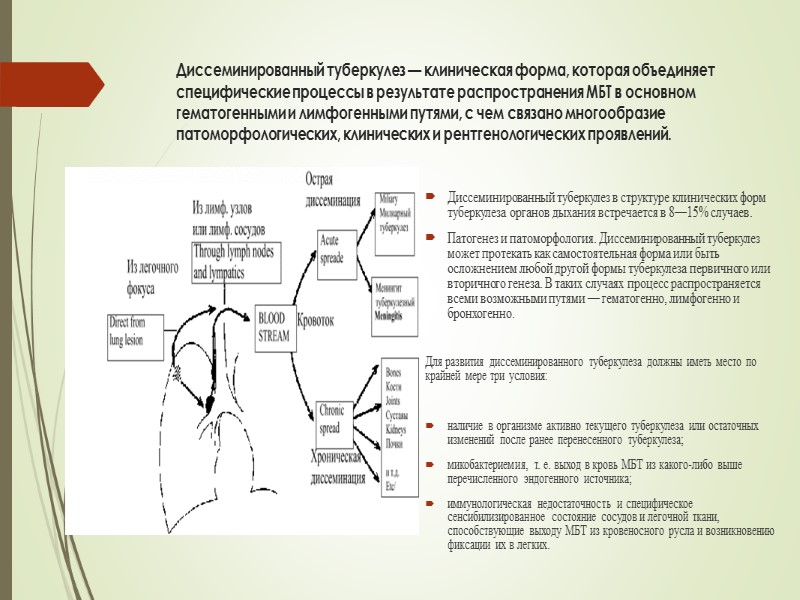

В клинической картине острого гематогенно диссеминированного туберкулеза преобладает